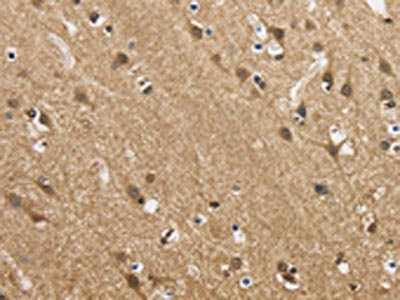

The image is immunohistochemistry of paraffin-embedded Human brain tissue using CSB-PA554215(GAS7 Antibody) at dilution 1/50. (Original magnification: ×200)